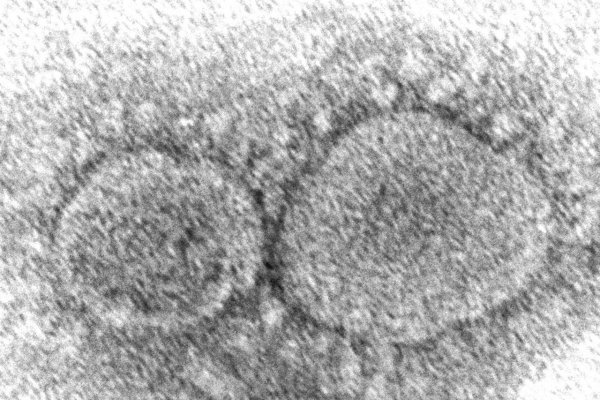

V Česku objavili prípady dvoch nových mutácií omikronu

.sita .svet 04.06.2022

Ide o varianty, ktoré spôsobili rast počtu nákaz v Portugalsku.